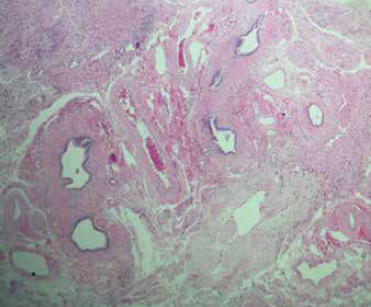

Paciente asintomático, sin alteraciones en los exámenes de laboratorio, por lo que se decidió alta ambulatoria. En la biopsia hepática (figuras 3 y 4) se reportó: hipoplasia hepática, espacios porta conservados con prominencia de los componentes vasculares, hepatocitos con cambios regenerativos y colestasis intracitoplasmática.

Imágenes: Núñez-Venzor et al.

Figura 3 Corte teñido con hematoxilina y eosina, en donde se identifican grupos de hepatocitos que alternan con vasos sanguíneos, escasos conductos biliares y zonas de fibrosis